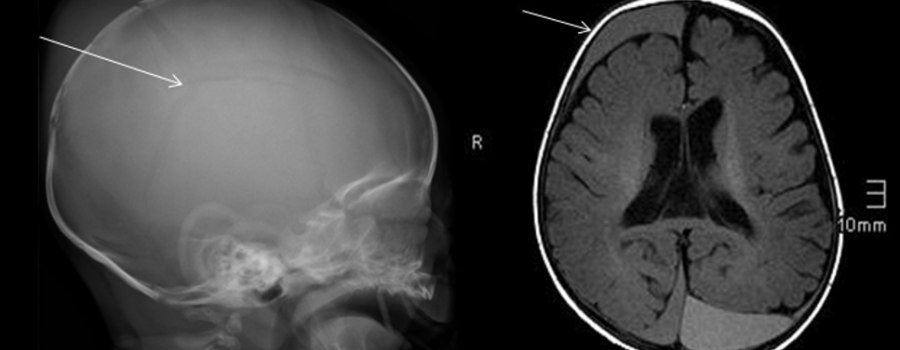

Kindesmisshandlung

Wenn hinter dem "Sturz" mehr steckt

Karl-Heinz Szeifert 19 Dec, 2018 00:00

Bei der Aufdeckung einer Kindesmisshandlung kommt der Kinderradiologie eine Schlüsselrolle zu. Ob die Verletzung eines Kindes durch Unfall oder Gewalt entstanden ist, kann meist erst mit Hilfe von Sonographie, Röntgen, Magnetresonanz- bzw. Computertomografie beurteilt werden.